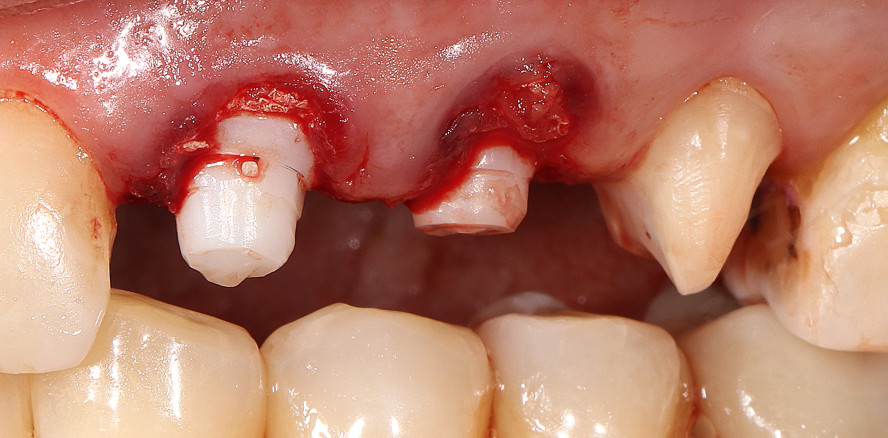

Nach schonender Extraktion der Zähne 23 und 24 (Abb. 5) unter Lokalanästhesie wurden die radikuläre Zyste und das inflammatorische Gewebe sorgfältig entfernt. Die Region wurde mit dem Ozon-DTA-Gerät für 60 Sekunden nachbehandelt. Die Aufbereitung des Implantatbetts erfolgte entsprechend der jeweiligen Knochenklasse. Nach Durchführung eines internen Sinuslifts konnten zwei einteilige Keramikimplantate der Länge 17 mm (SDS) in die Regionen 23 und 24 mit einem Drehmoment von 35 Ncm primärstabil eingesetzt werden (Abb. 6). Im Bereich der Kompakta wurde durch eine überdimensionierte Implantatbettaufbereitung eine druckbedingte Einschränkung der lokalen Durchblutung durch das Implantat vermieden. Die Primärstabilität wurde durch ein aggressives „Makrogewinde“ an der Implantatspitze, das gleichzeitig als Knochenkondensator auf die Spongiosa wirkt, erreicht. Die sofortige Überprüfung mit dem Periotest-Gerät ergab Werte von –5,5 am Implantat 23 und –6,7 am Implantat 24, ein messbarer Hinweis für gute Stabilität. Um die Wundheilung und Regeneration von Knochen und Weichgewebe zu fördern, wurden fünf A-PRF-Membranen (nach dem Konzept von Dr. Joseph Choukroun), hergestellt aus dem Eigenblut der Patientin, eingesetzt (Abb. 7 und 8).36,37